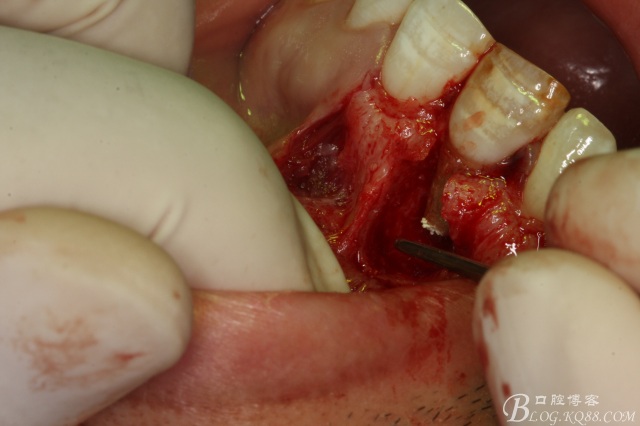

圖7.去除囊壁及肉芽組織